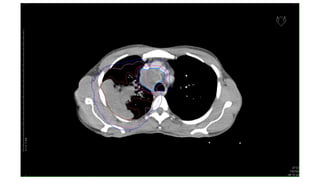

CT images of Ca Lungs

NSCLC

Ca Left Lung post NACT with residual